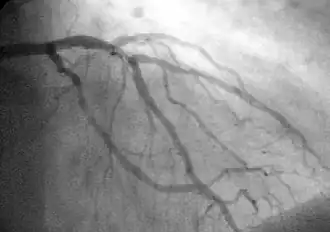

A coronary angiogram (an X-ray with radiocontrast agent in the coronary arteries) that shows the left coronary circulation. The distal left main coronary artery (LMCA) is in the left upper quadrant of the image. Its main branches (also visible) are the left circumflex artery (LCX), which courses top-to-bottom initially and then toward the centre/bottom, and the left anterior descending (LAD) artery, which courses from left-to-right on the image and then down the middle of the image to project underneath the distal LCX. The LAD, as is usual, has two large diagonal branches, which arise at the centre-top of the image and course toward the centre/right of the image.

Coronary Angiography (CAG[3]).